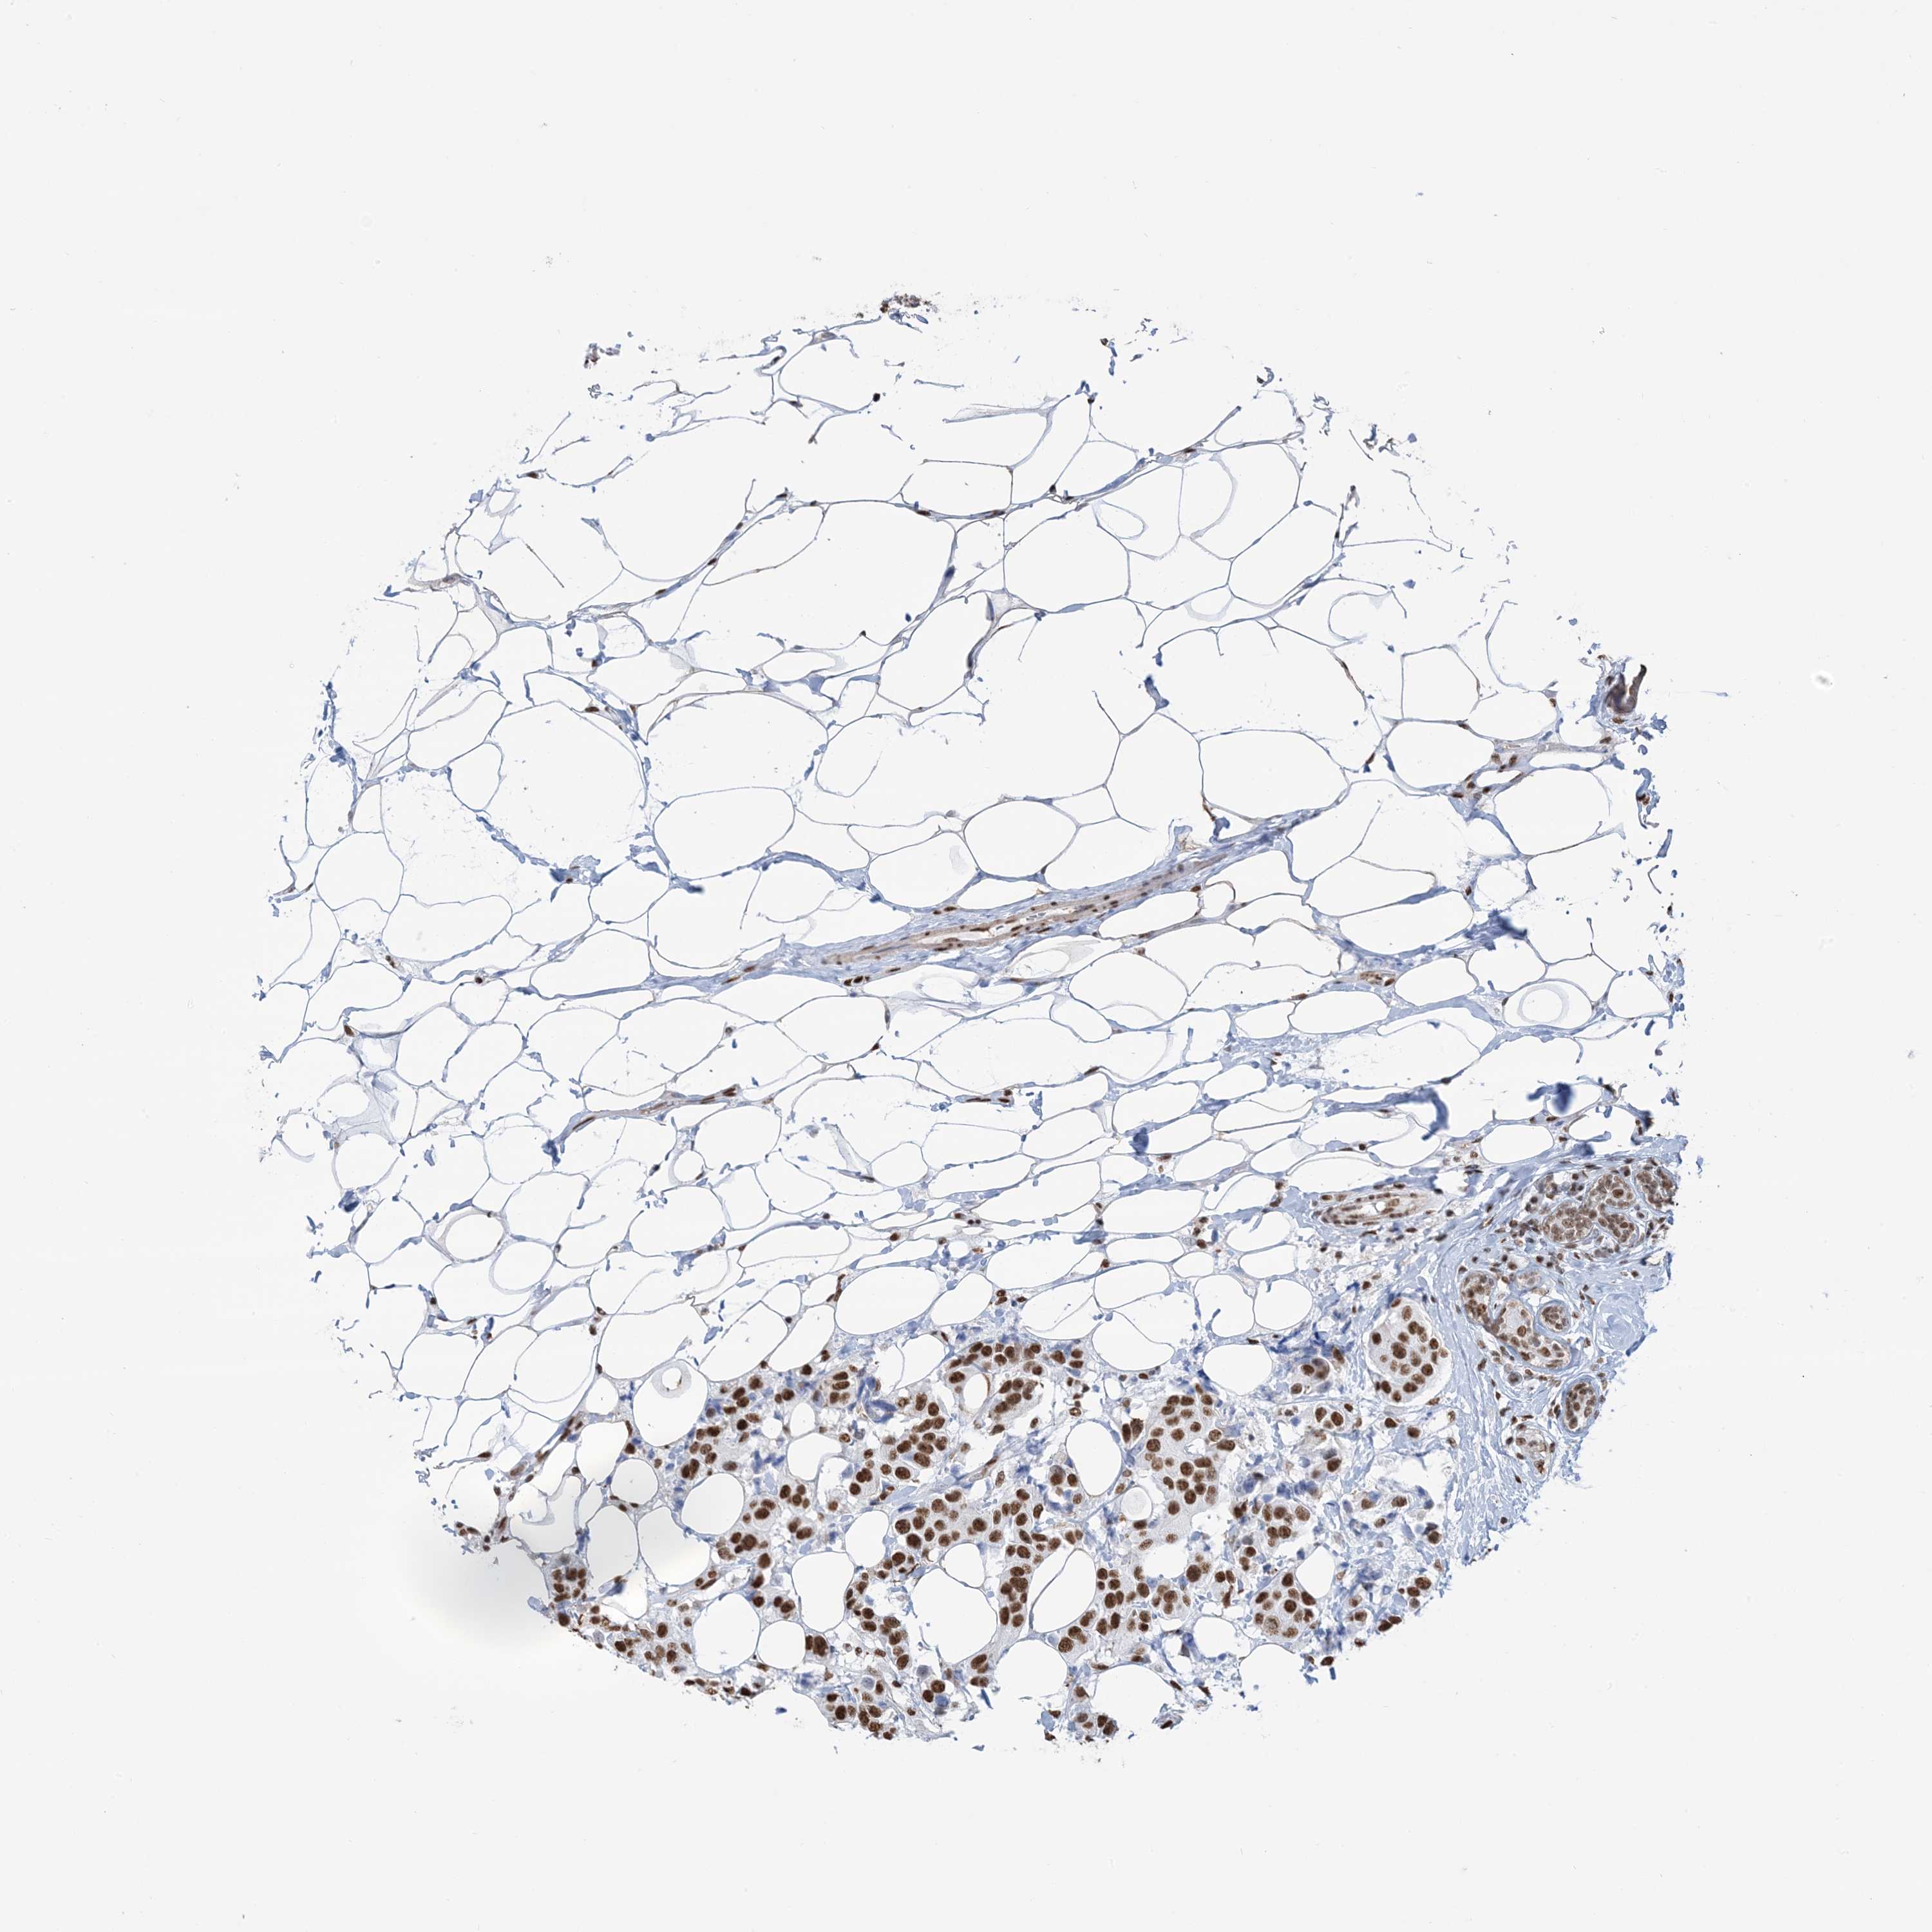

BRCA TCGA BRCA VALIDATION PROTEIN EXPRESSION